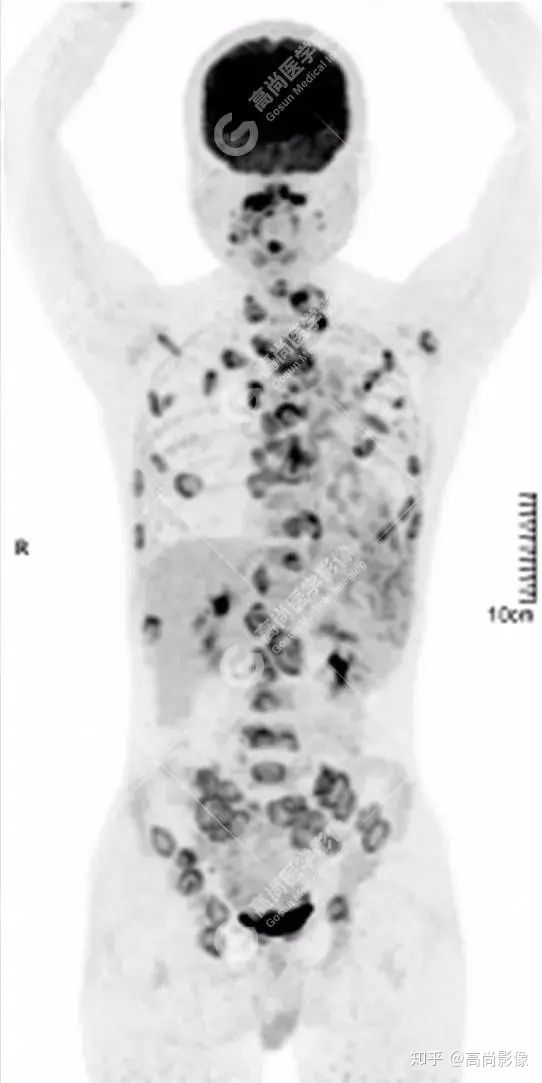

PET/CT 全身圖

脊柱多發(fā)椎體及附件骨質(zhì)破壞,代謝不均性增高

全身多處骨質(zhì)破壞,代謝不均性增高

全身多發(fā)高代謝腫大淋巴結(jié),中央代謝缺損

【PET/CT提示】雙肺、左側(cè)胸膜多發(fā)結(jié)節(jié)影,全身多處骨質(zhì)破壞,全身多發(fā)淋巴結(jié)腫大,代謝攝取不均勻性增高。